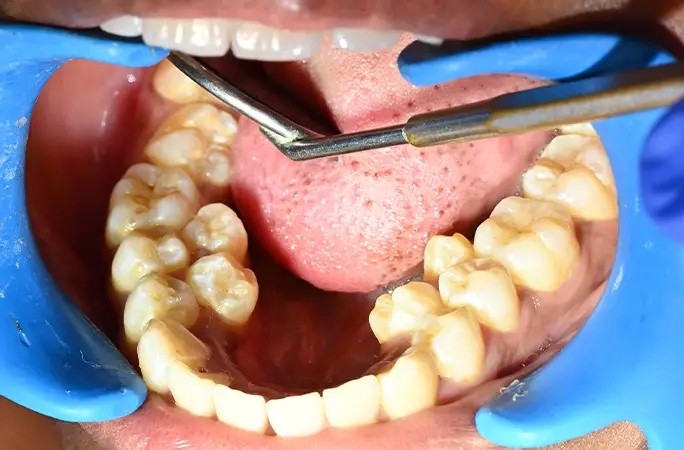

У девушки на шесть зубов больше, чем у большинства людей: у жительницы Индии насчитали 38 зубов вместо 32-ух. При этом у неё нашли ещё два зуба, которые не прорезались. Больше только у мужчины из Канады — 41 штука.

По словам Калпаны, эти лишние зубы у нее с юности. Родители девушки рекомендовали ей удалить лишние зубы, однако она побоялась. Кроме того, дополнительные зубы не доставляли Калпане никакого неудобства, и она решила их сохранить.